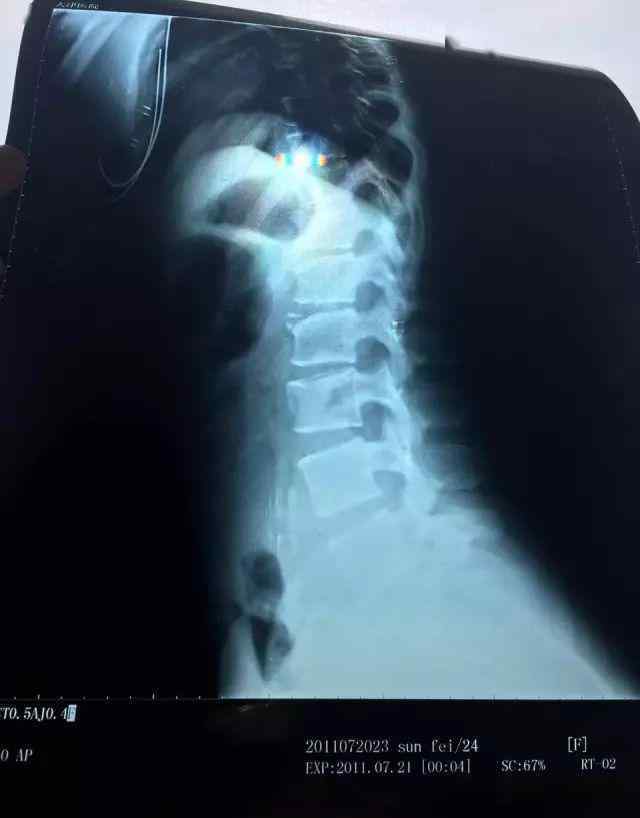

故事从2011年开始,当时一场演出事故导致孙飞胸椎爆裂骨折和腰椎压缩性骨折。那年她才23岁!

孙飞从6岁开始练习,在过去的17年里经历了无数次韧带撕裂,在不断挑战身体极限的6000多个昼夜中幸存下来。